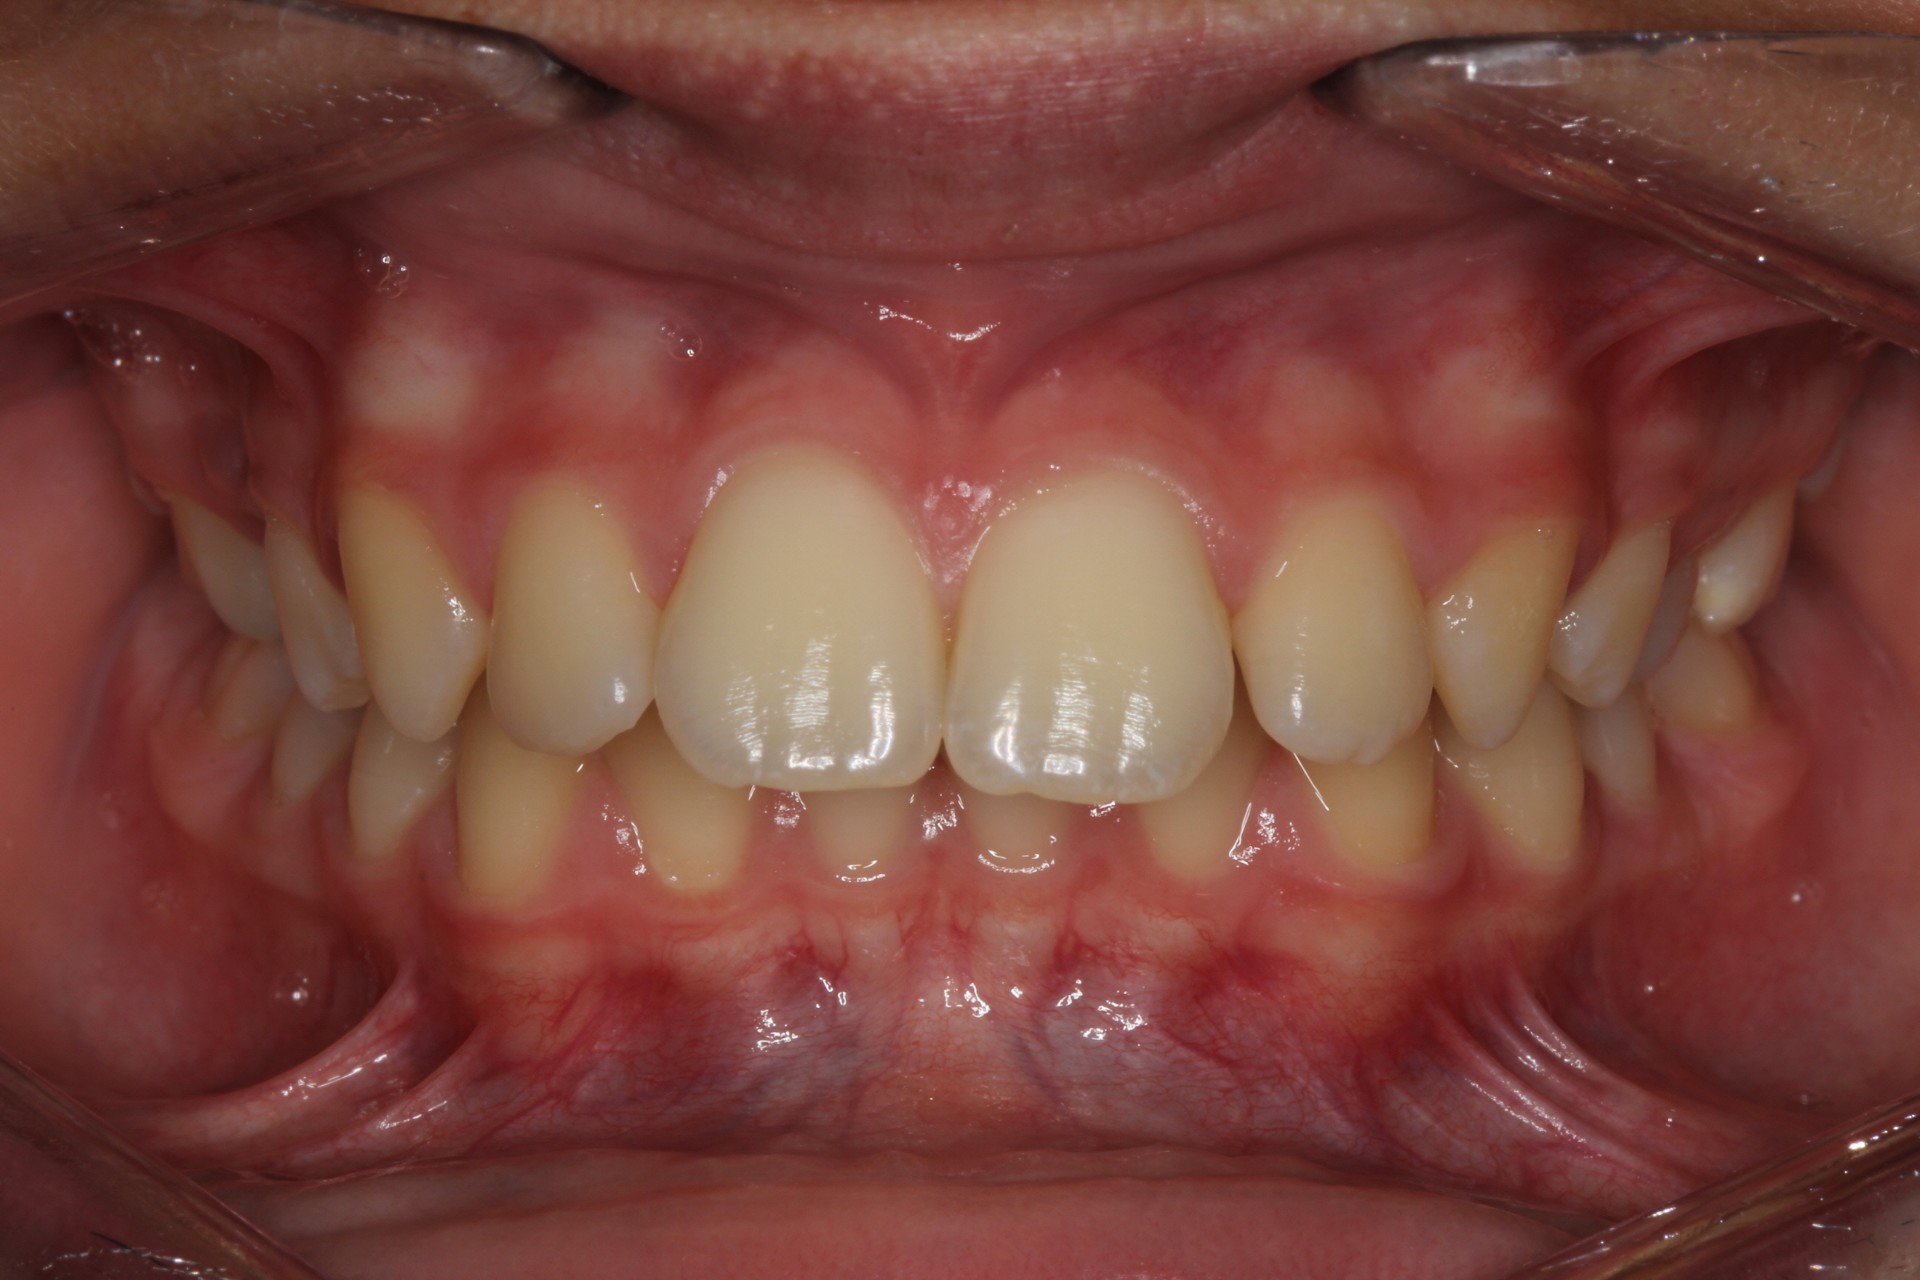

Protruding front teeth and spacing – Child case